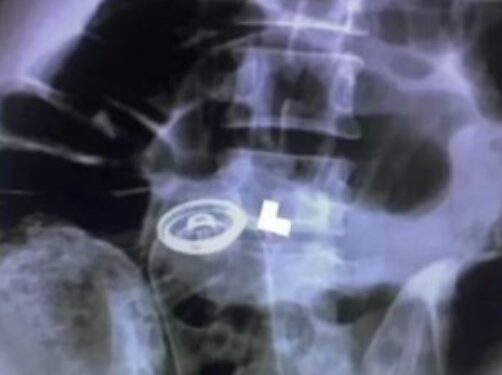

Os médicos responsáveis pelo caso optaram por realizar a remoção do objeto por meio de um procedimento de emergência, guiado por raio-X. Devido à intensidade da dor relatada pelo paciente, não foi possível realizar exames complexos para avaliar completamente a situação antes da intervenção cirúrgica.